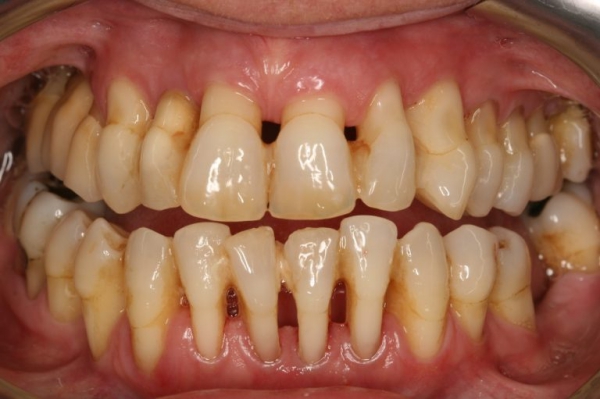

上圖中箭頭所指處因牙齦下結石堆積,因而造成牙齦呈現紅腫狀態。

經由牙周治療去除結石後可見牙齦恢復健康,呈現粉紅色且不再紅腫,但牙齦

消腫後會造成牙齦萎縮,而萎縮程度跟齒槽骨破壞程度相關。